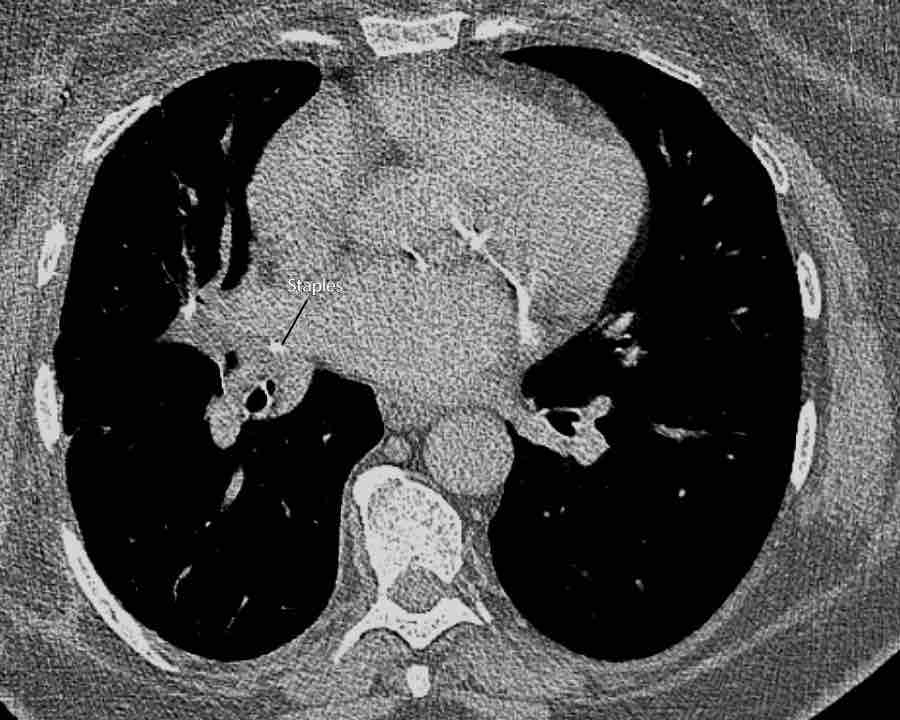

Hình ảnh

Cuộn qua các hình ảnh.

Phế quản thùy trên, phế quản trung gian và phế quản thùy dưới tiếp tục đi về phía ngoại vi.

Phế quản thùy giữa kết thúc tại vị trí đặt các ghim phẫu thuật.